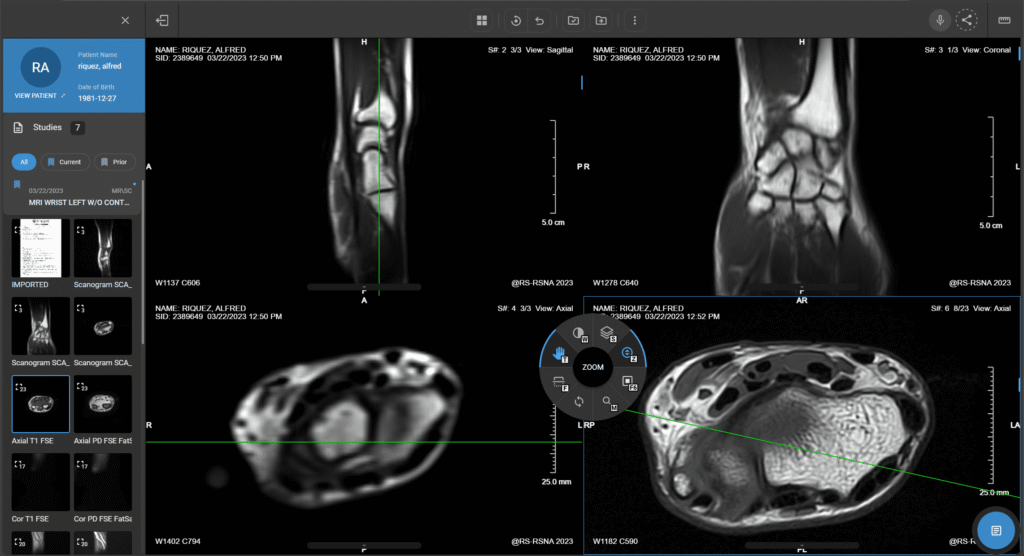

La Unidad de Imagen Corporal de EXTOM está orientada a la evaluación integral de órganos sólidos, abdomen, pelvis y estructuras vasculares, con protocolos diseñados para alta precisión diagnóstica. Mediante tomografía y resonancia magnética, caracterizamos lesiones focales, inflamación, patología vascular y escenarios oncológicos, aportando información clave para diagnóstico, estadificación y seguimiento. Nuestro enfoque prioriza la selección adecuada del estudio según la pregunta clínica, la optimización de parámetros técnicos y la elaboración de reportes claros con hallazgos accionables. La unidad es especialmente útil en dolor abdominal, sospecha de enfermedad hepática o pancreática, evaluación urológica, y control evolutivo de pacientes oncológicos. Mantenemos un estándar de calidad, seguridad y trazabilidad para respaldar decisiones clínicas oportunas.

Tomografía y resonancia para patología abdominal y pélvica compleja

Ajustamos fases de contraste, secuencias y reconstrucciones para responder a la indicación clínica y mejorar la caracterización del hallazgo.